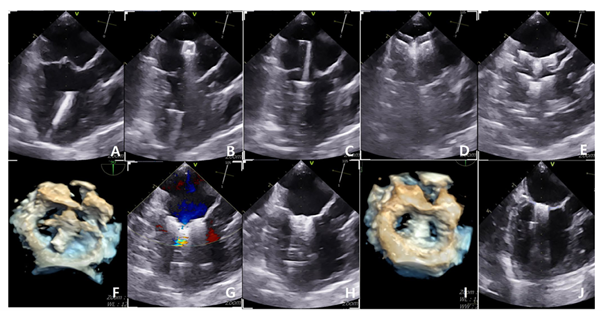

이번에 발표된 연구에는 KAMC에서 TEER 수술을 받은 8살에서 14살의 체중 2.05kg부터 7.8kg까지의 이첨판 페쇄부전증(MMVD) B2, C, D단계의 개들이 포함됐다. 논문에는 TEER 수술을 받은 개에서 수술 전과 3개월에 걸쳐 나타나는 이첨판 역류량(Regurgitatn volume), 심장 크기, 처방 약물 등의 변화, 합병증을 자세히 설명하고 있다.

연구 결과에 따르면, 실제로 TEER 수술 이후 3개월 차에 이첨판 역류량이 3.96ml/kg에서 1.25ml/kg까지 감소하는 모습을 보였으며, 좌심방 대동맥 비율(LA/AO), 체표면적 보정 좌심실 이완기 내경(LVIDDn) 등 좌심의 용적 과부하를 의미하는 지표들의 유의미한 개선이 확인됐다.

이정민 수의사는 “이첨판 폐쇄부전증의 관리에서 환자에게 약물적 관리가 더 적절한지, 또는 수술적 치료를 고려해야 하는지를 정확히 평가하는 것이 중요하다”고 강조하면서 “이러한 요소들을 판단하기 위해 경식도 초음파를 통한 3D 심장 재구성이 큰 도움이 된다”고 밝혔다.

경식도 초음파를 활용해 정밀한 심장 구조 및 역류량을 평가할 경우 이첨판 폐쇄부전증 환자에게 보다 명확하고 적극적인 맞춤형 처방이 가능하다. 또한 TEER 수술에 있어 내과, 외과, 영상의학과, 마취과, 중환자응급의학과 간의 긴밀한 협진 역시 치료 결과에 중대한 영향을 미친다.